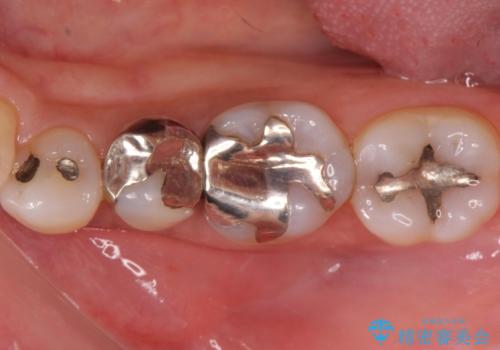

- 症状はないものの、検査の結果右上の奥歯が大きく割れていることが確認されたケースです。

無症状であったため放置していた結果、歯の周囲の骨が溶けてなくなっていました。